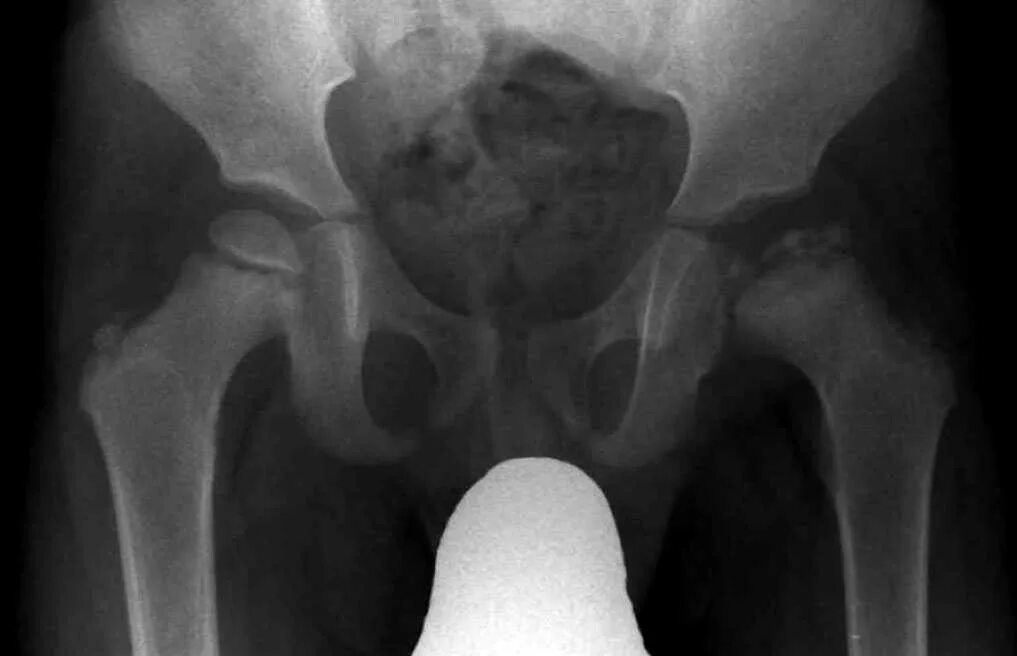

Некроз головки тазобедренного сустава лечение